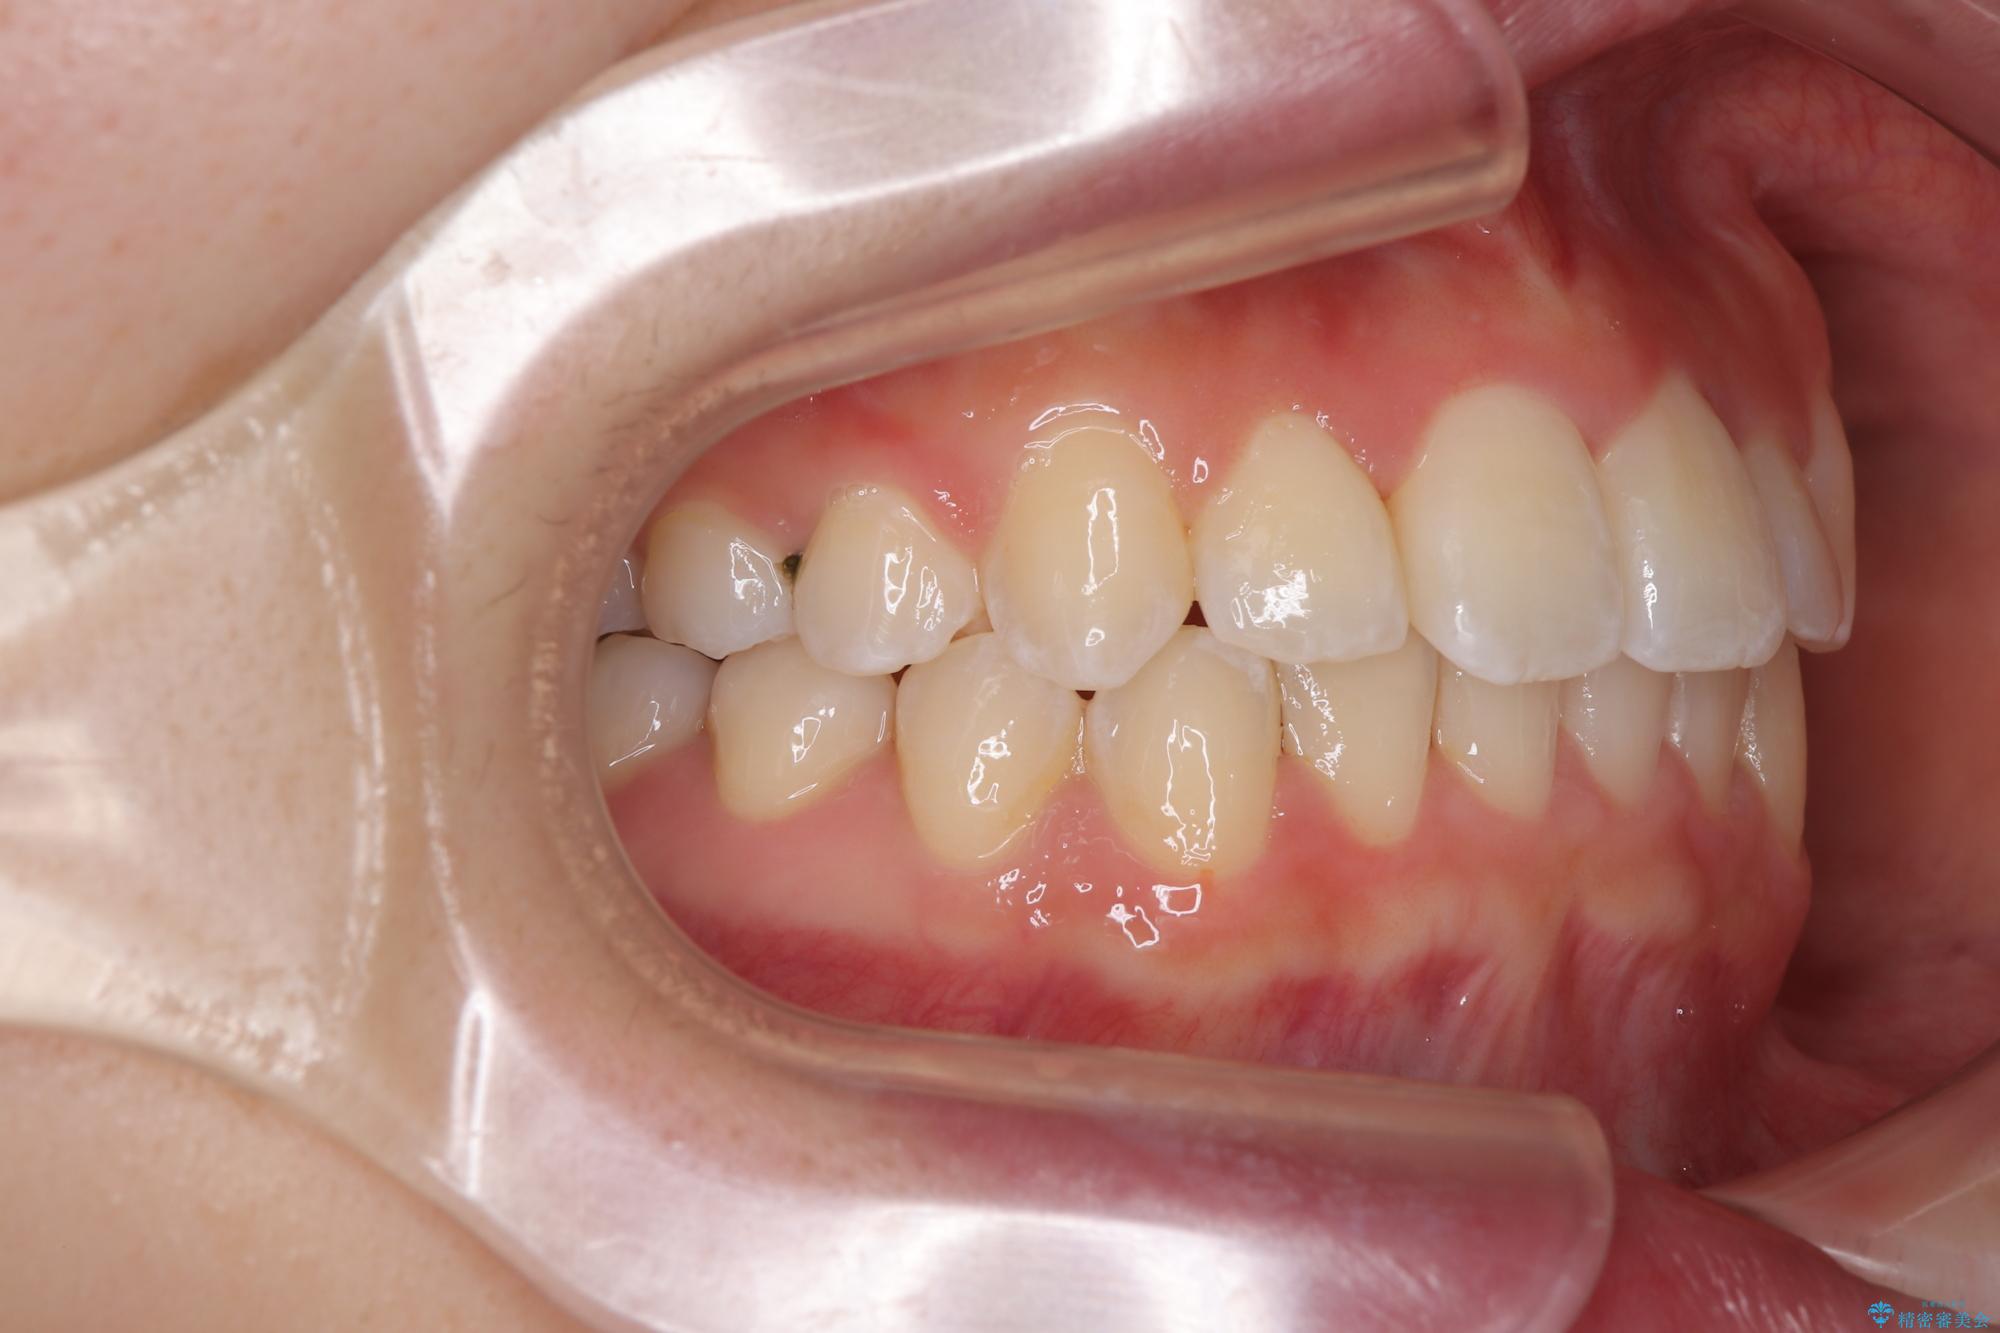

前歯のクロスバイト 裏側に隠れた歯をワイヤー装置で短期間治療

- 上顎前歯のクロスバイトを気にして来院された患者様です。

ワイヤー矯正でもマウスピース矯正でも対応可能でしたが、マウスピースによる自己管理に一切の自信がないとのことで、ワイヤー装置にて矯正治療を行うこととしました。